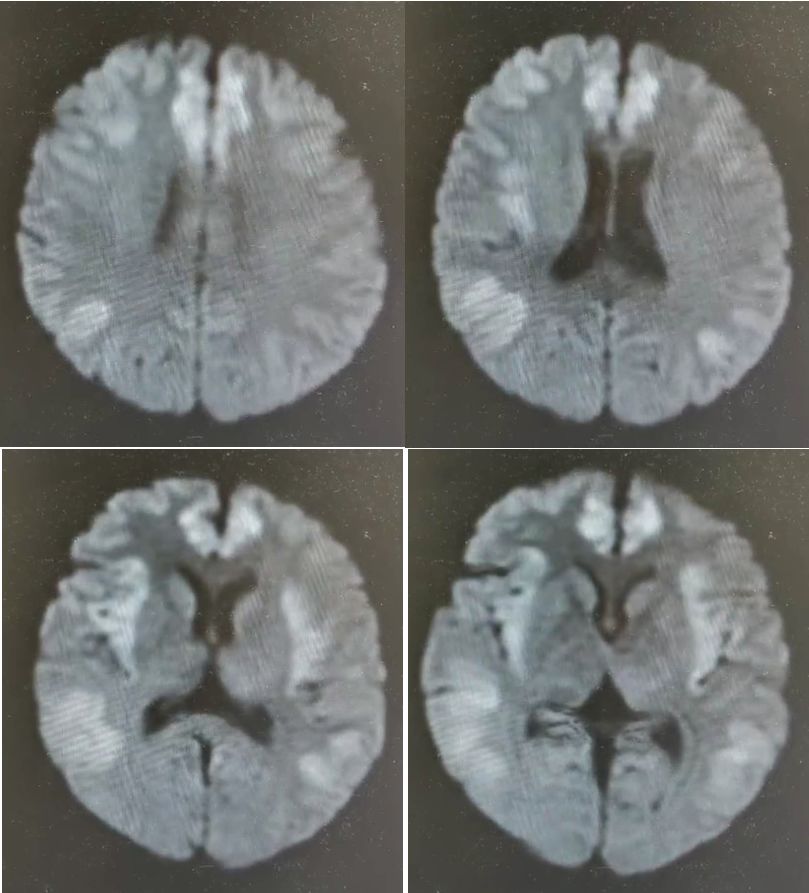

影像可见:MRI的Flair像(A,B)显示额叶下前内侧广泛的血管性水肿,T1像(C)显示双侧额叶软脑膜和实质增强。治疗后7个月(D,E)分别显示血管源性水肿和增强的消退。

诊断: 神经结节病。

神经结节病(neurosarcoidosis)磁共振脑表现为广泛的双额叶水肿和强化(图A-C)。

回顾过去,7年前,他有一个颈部肿块和肉芽肿活检,但从未接受过治疗结节病。

口服泼尼松和甲氨蝶呤后,临床症状和MRI异常(图,D和E)有所改善,并被诊断为可能的神经结节病。

神经结节病是一种罕见的嗅觉缺失的病因,但需要作为一种不同的考虑因素。结节病中的嗅觉缺失是由鼻阻塞或嗅上皮、球或束的神经结节病引起的。

这个病例提示我们:一是嗅觉减退要注意颅内、额底病变;二是嗅觉减退可以作为神经结节病的首发症状。